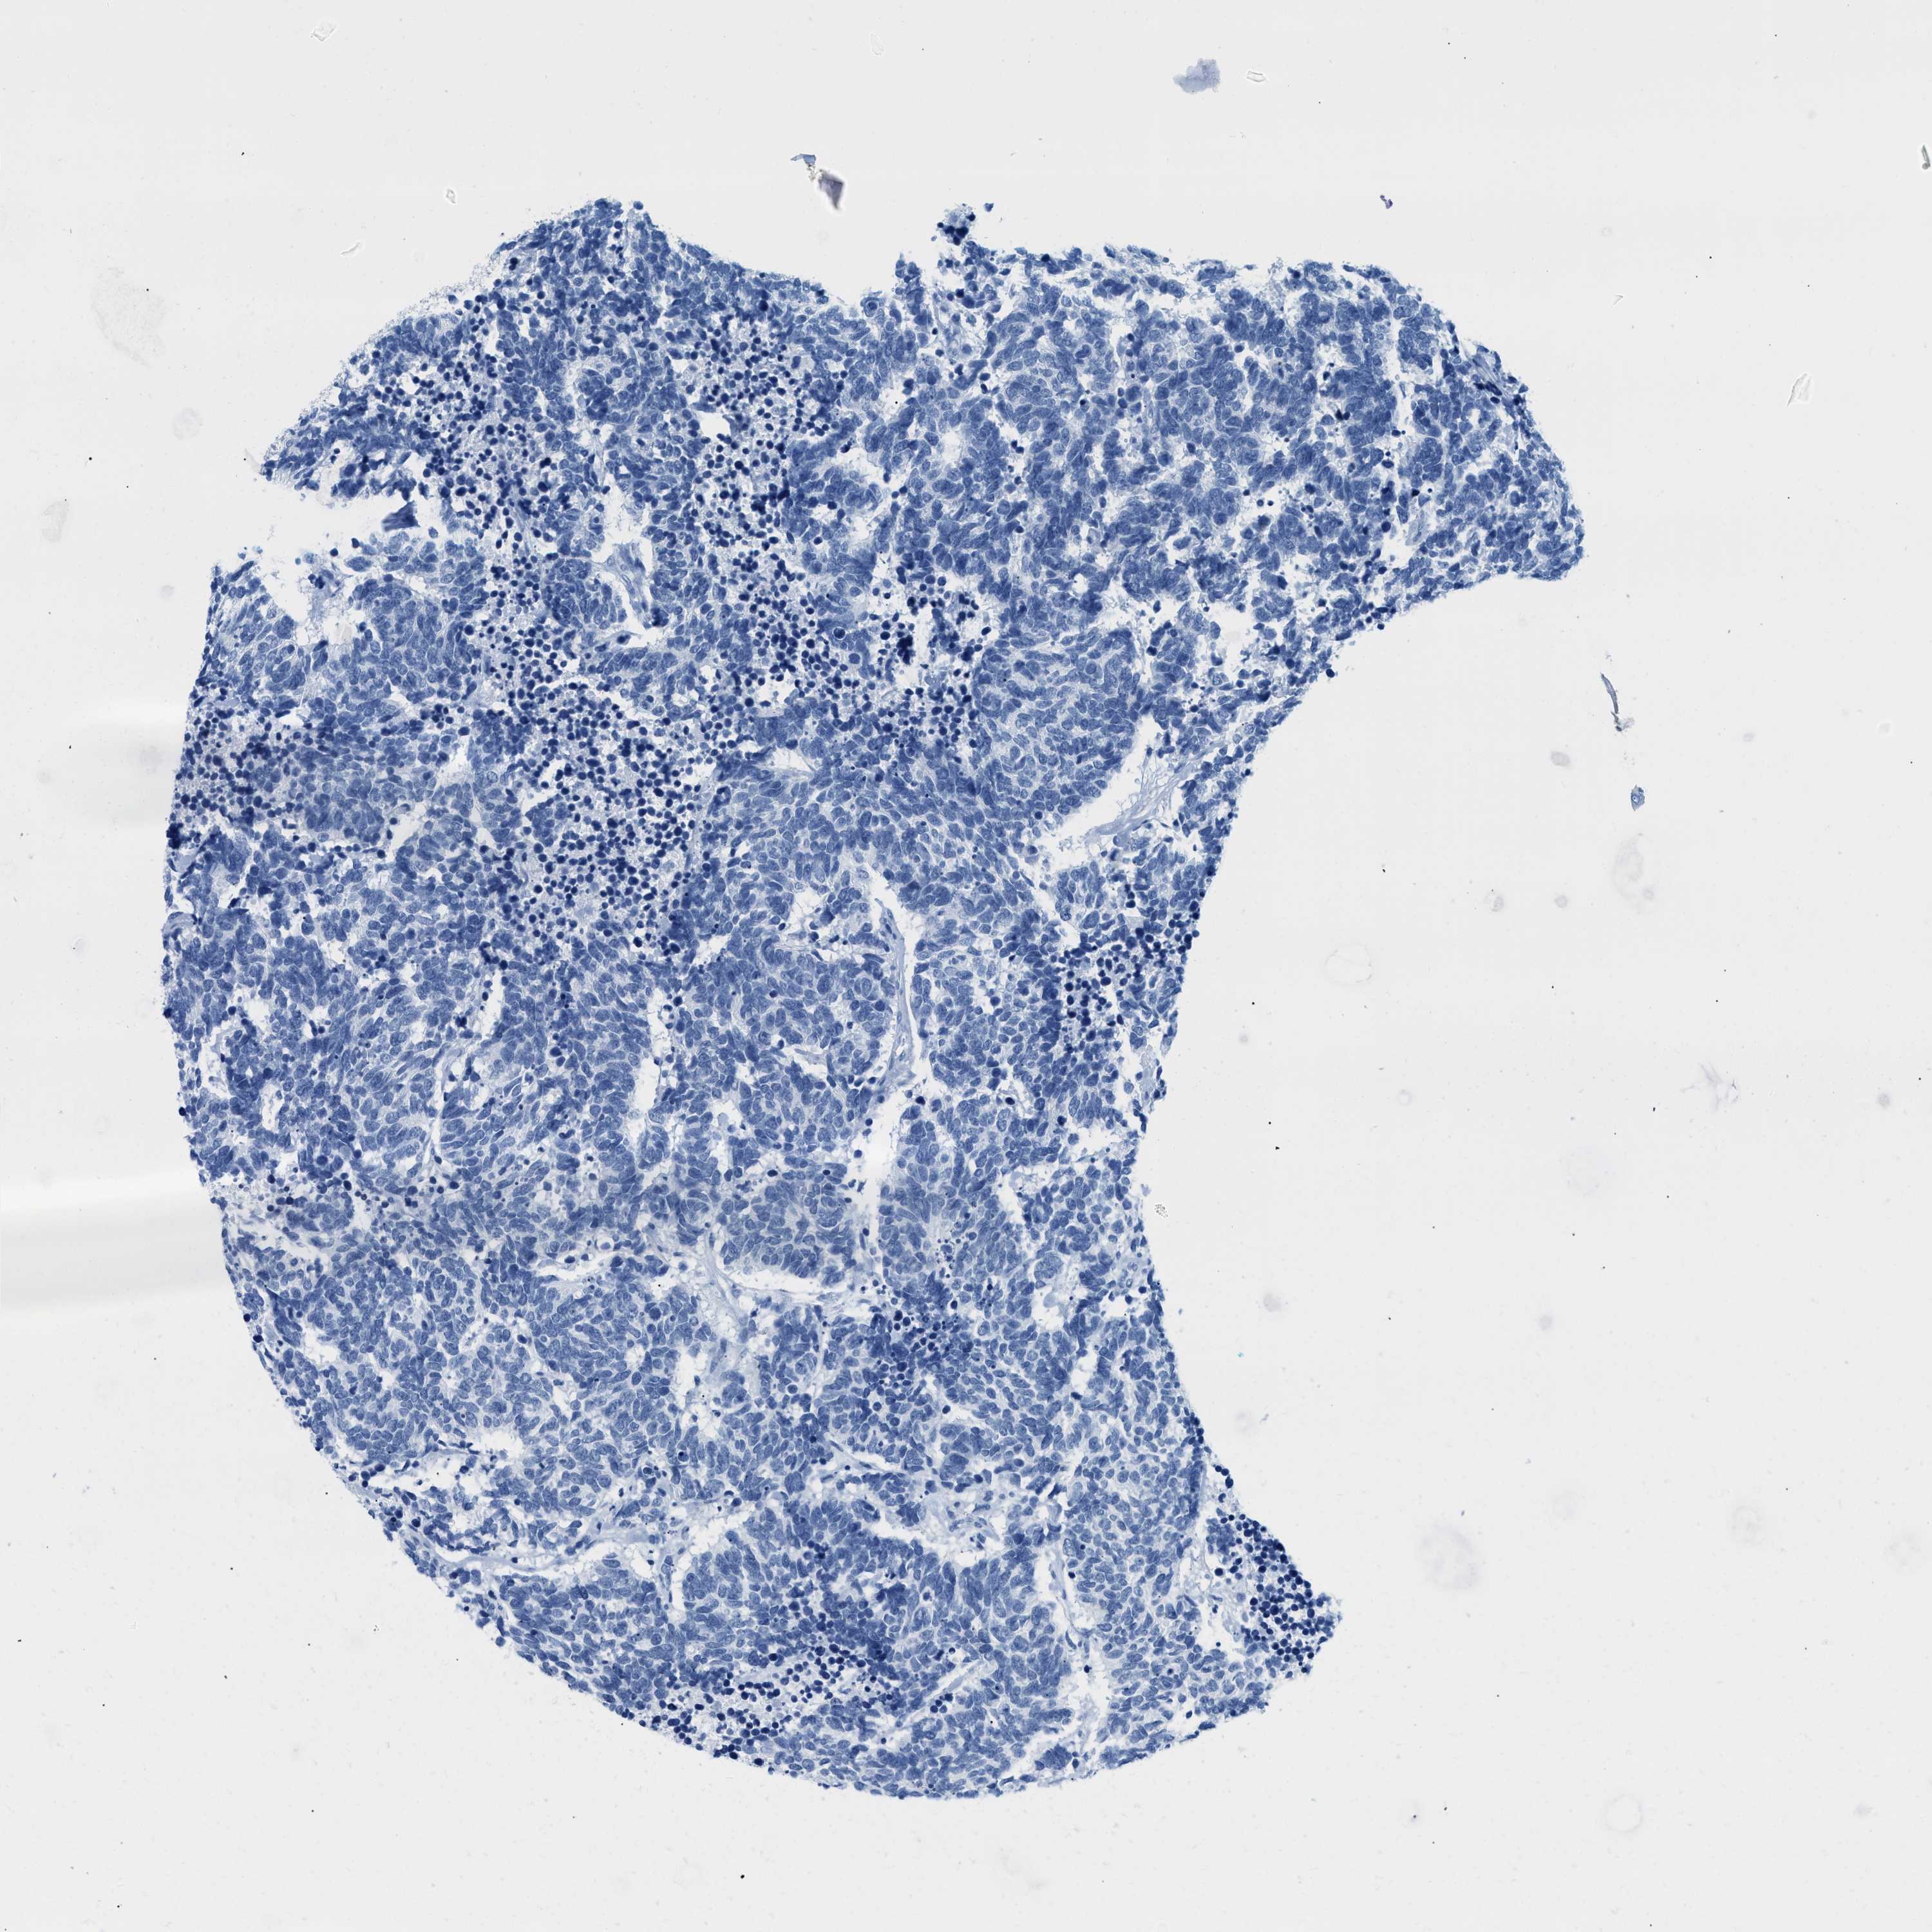

CARCINOID - Protein expressioni

A mouse-over function shows sample information and annotation data. Click on an image to view it in a full screen mode. Samples can be filtered based on level of antibody staining by selecting one or several of the following categories: high, medium, low and not detected. The assay and annotation is described here.

Each image is clickable and will lead to virtual microscopy that enables deeper exploration of all samples and also displays staining intensity scores, fraction scores and subcellular localization as well as patient and tissue information for each sample.

Antibody CAB016728

Staining

High

Medium

Low

Not detected

Carcinoid, malignant, NOS